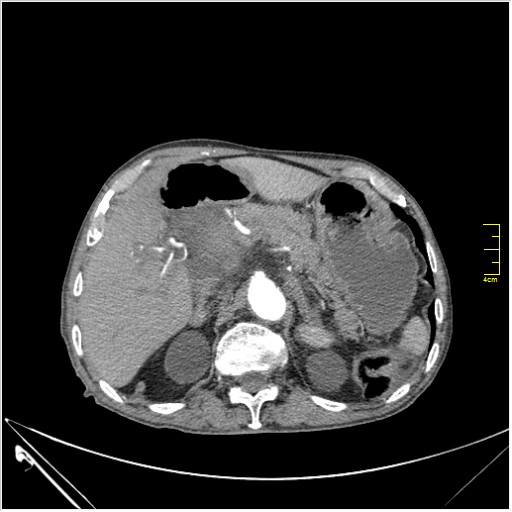

Huge abdominal aorta aneurism. Simple renal cortical cysts (Bosniak type 1).